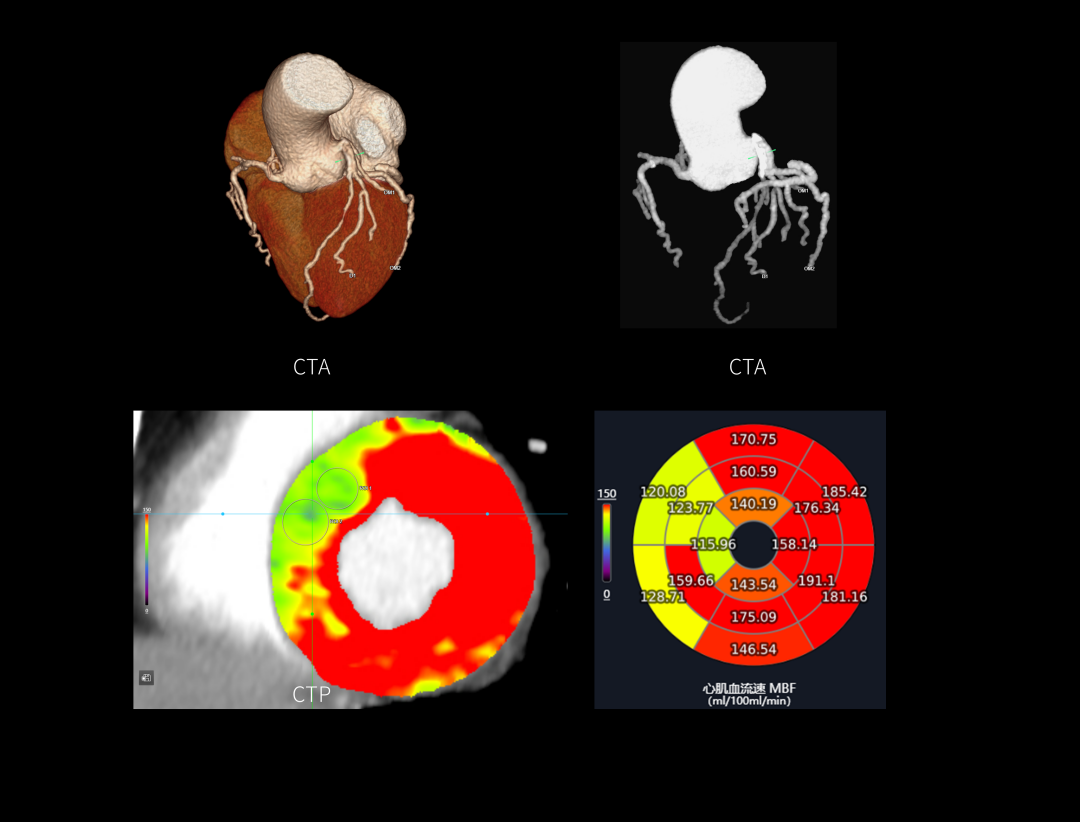

299,520个探测器单元构成了16cm的宽体时空探测器,采集海量原始数据,从源头提升成像质量,精微显示细小结构